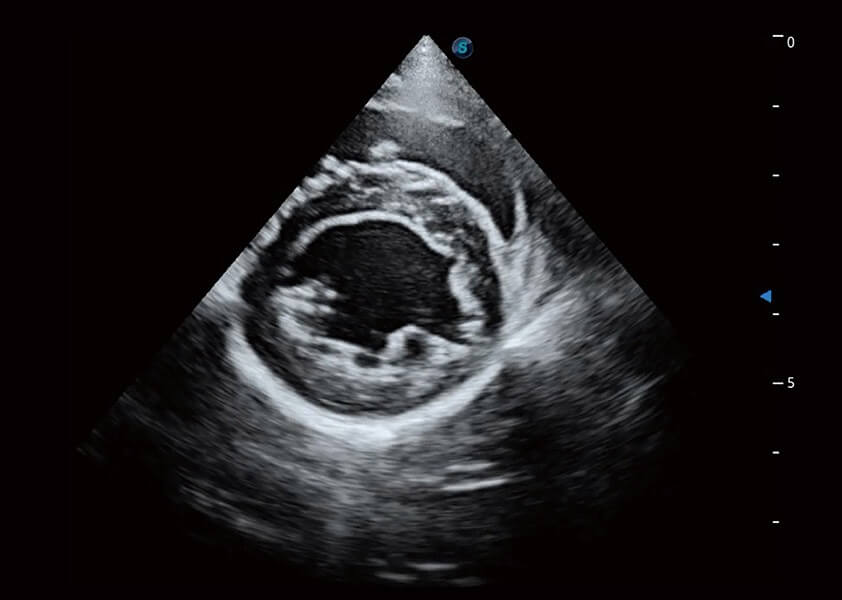

優(yōu)異的基礎(chǔ)圖像

(犬)乳頭肌短軸